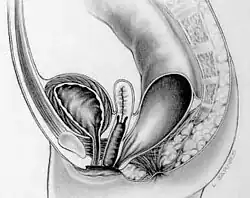

Свищ, или фи́стула (от лат. fistula «трубка»), — канал, соединяющий полости тела (в том числе патологические) или полые органы с внешней средой или между собой. Обычно имеет вид узкого канала, выстланного эпителием или грануляционной тканью.

- Свищ ректовагинальный — повреждение ректовагинальной перегородки